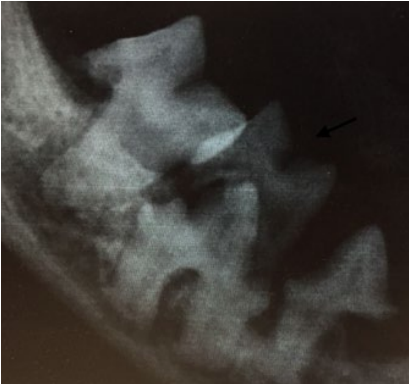

- Отсутствие постоянного преемника – состояние, при котором отсутствуют зачатки постоянных зубов (фото 3):

- гиподентия – отсутствие от одного до пяти постоянных зубов;

- олигодентия – отсутствие более пяти единиц постоянных зубов;

- адентия – полное отсутствие зубов.